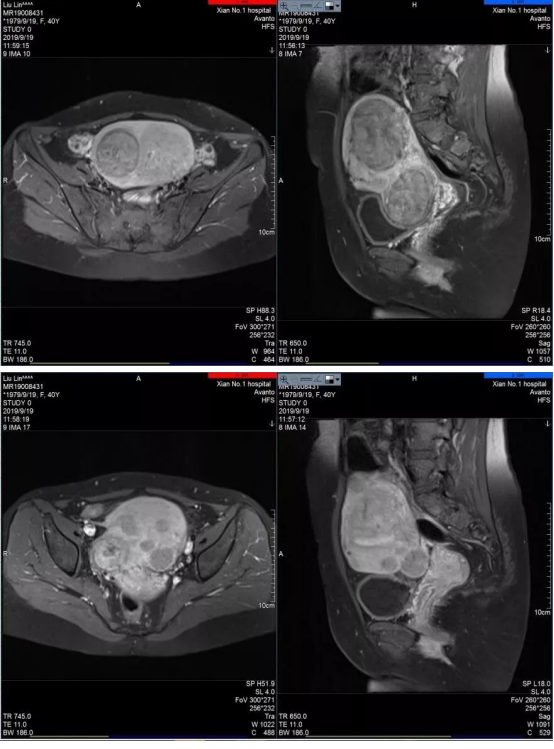

海扶刀治疗再创佳绩!成功完成一例多发性子宫肌瘤合并子宫腺肌症患者的海扶消融